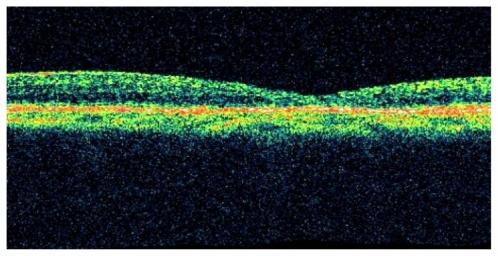

A case report with optical coherence tomography (OCT) scans prior to surgery, at 20 minutes postoperatively and then at 17 hours postoperatively.

OCT images of a 73-year-old woman with a stage 3 macular hole were obtained. At 20 minutes postoperatively, there was a reduction in intraretinal cysts and a reduction in macular hole size with elevated-open configuration. At 17 hours postoperatively, complete macular hole closure was noted.

OCT Images of a macular hole in the early postoperative period have been successfully obtained. Macular holes can close within 24 hours postoperatively and show morphological changes that may be predictive of closure within 20 minutes postoperatively.